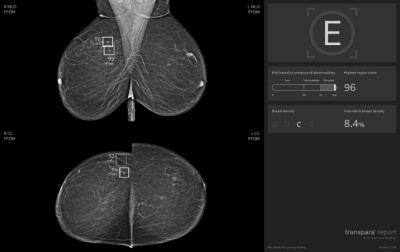

„Během společného projektu standardně posuzovali každý snímek dva lékaři. Novinkou ale bylo třetí čtení pořízených snímků za pomoci umělé inteligence. Živí odborníci tak získali možnost porovnat svůj nález s doporučením strojového algoritmu, který se učil na milionech snímků uložených v centrální evidenci. Během pilotního projektu jsme si chtěli ověřit, že zapojení AI pomůže snížit riziko přehlédnutí nádorových změn a ulehčí lékařům práci. Podpora a spolupráce s OZP pro nás byla zásadní. Díky ní jsme mohli pacientkám poskytovat vyšetření s využitím AI v běžném provozu a sledovat tak skutečné přínosy i dopady na praxi,“ popisuje prof. MUDr. Jan Daneš, CSc., vysokoškolský profesor a odborník v oboru radiologie a mamodiagnostiky z Mamodiagnostického centra Waltrovka a Beroun, člen skupiny EUC.

Zvýšený zájem o vyšetření se zapojením umělé inteligence při prevenci rakoviny prsu dokládají statistiky loňského a letošního roku Mamodiagnostických center Waltrovka a Beroun. V roce 2024 o něj projevilo zájem 54 % pacientek (celkem 26 481, z toho s využitím AI 14 293), v roce 2025 už se jedná téměř o 74 % (dosud celkem 18 890, z toho AI 13 993). Špičková technologie se tak prakticky během jednoho roku v praxi stala standardem. Lékaři zároveň potvrzují zvýšení záchytu nádorů o zhruba 16,7 %, což odpovídá i výsledkům zahraničních studií.

„Umělá inteligence má mimořádně vysokou přesnost. Negativní prediktivní hodnota dosahuje 99,97 procenta. U naprosté většiny snímků tedy dokáže spolehlivě vyloučit přítomnost nádoru, což snižuje stres a šetří čas pacientek i hodnotitelů,“ popisuje profesor Daneš a doplňuje: „Osobně si nesmírně vážím ještě jedné skutečnosti. Přes počáteční zdrženlivost stoupla důvěra lékařů v technologii během dvou let z 25 % prakticky na 100 %. Dnes už si běžné čtení snímků bez podpory AI neumíme představit.“